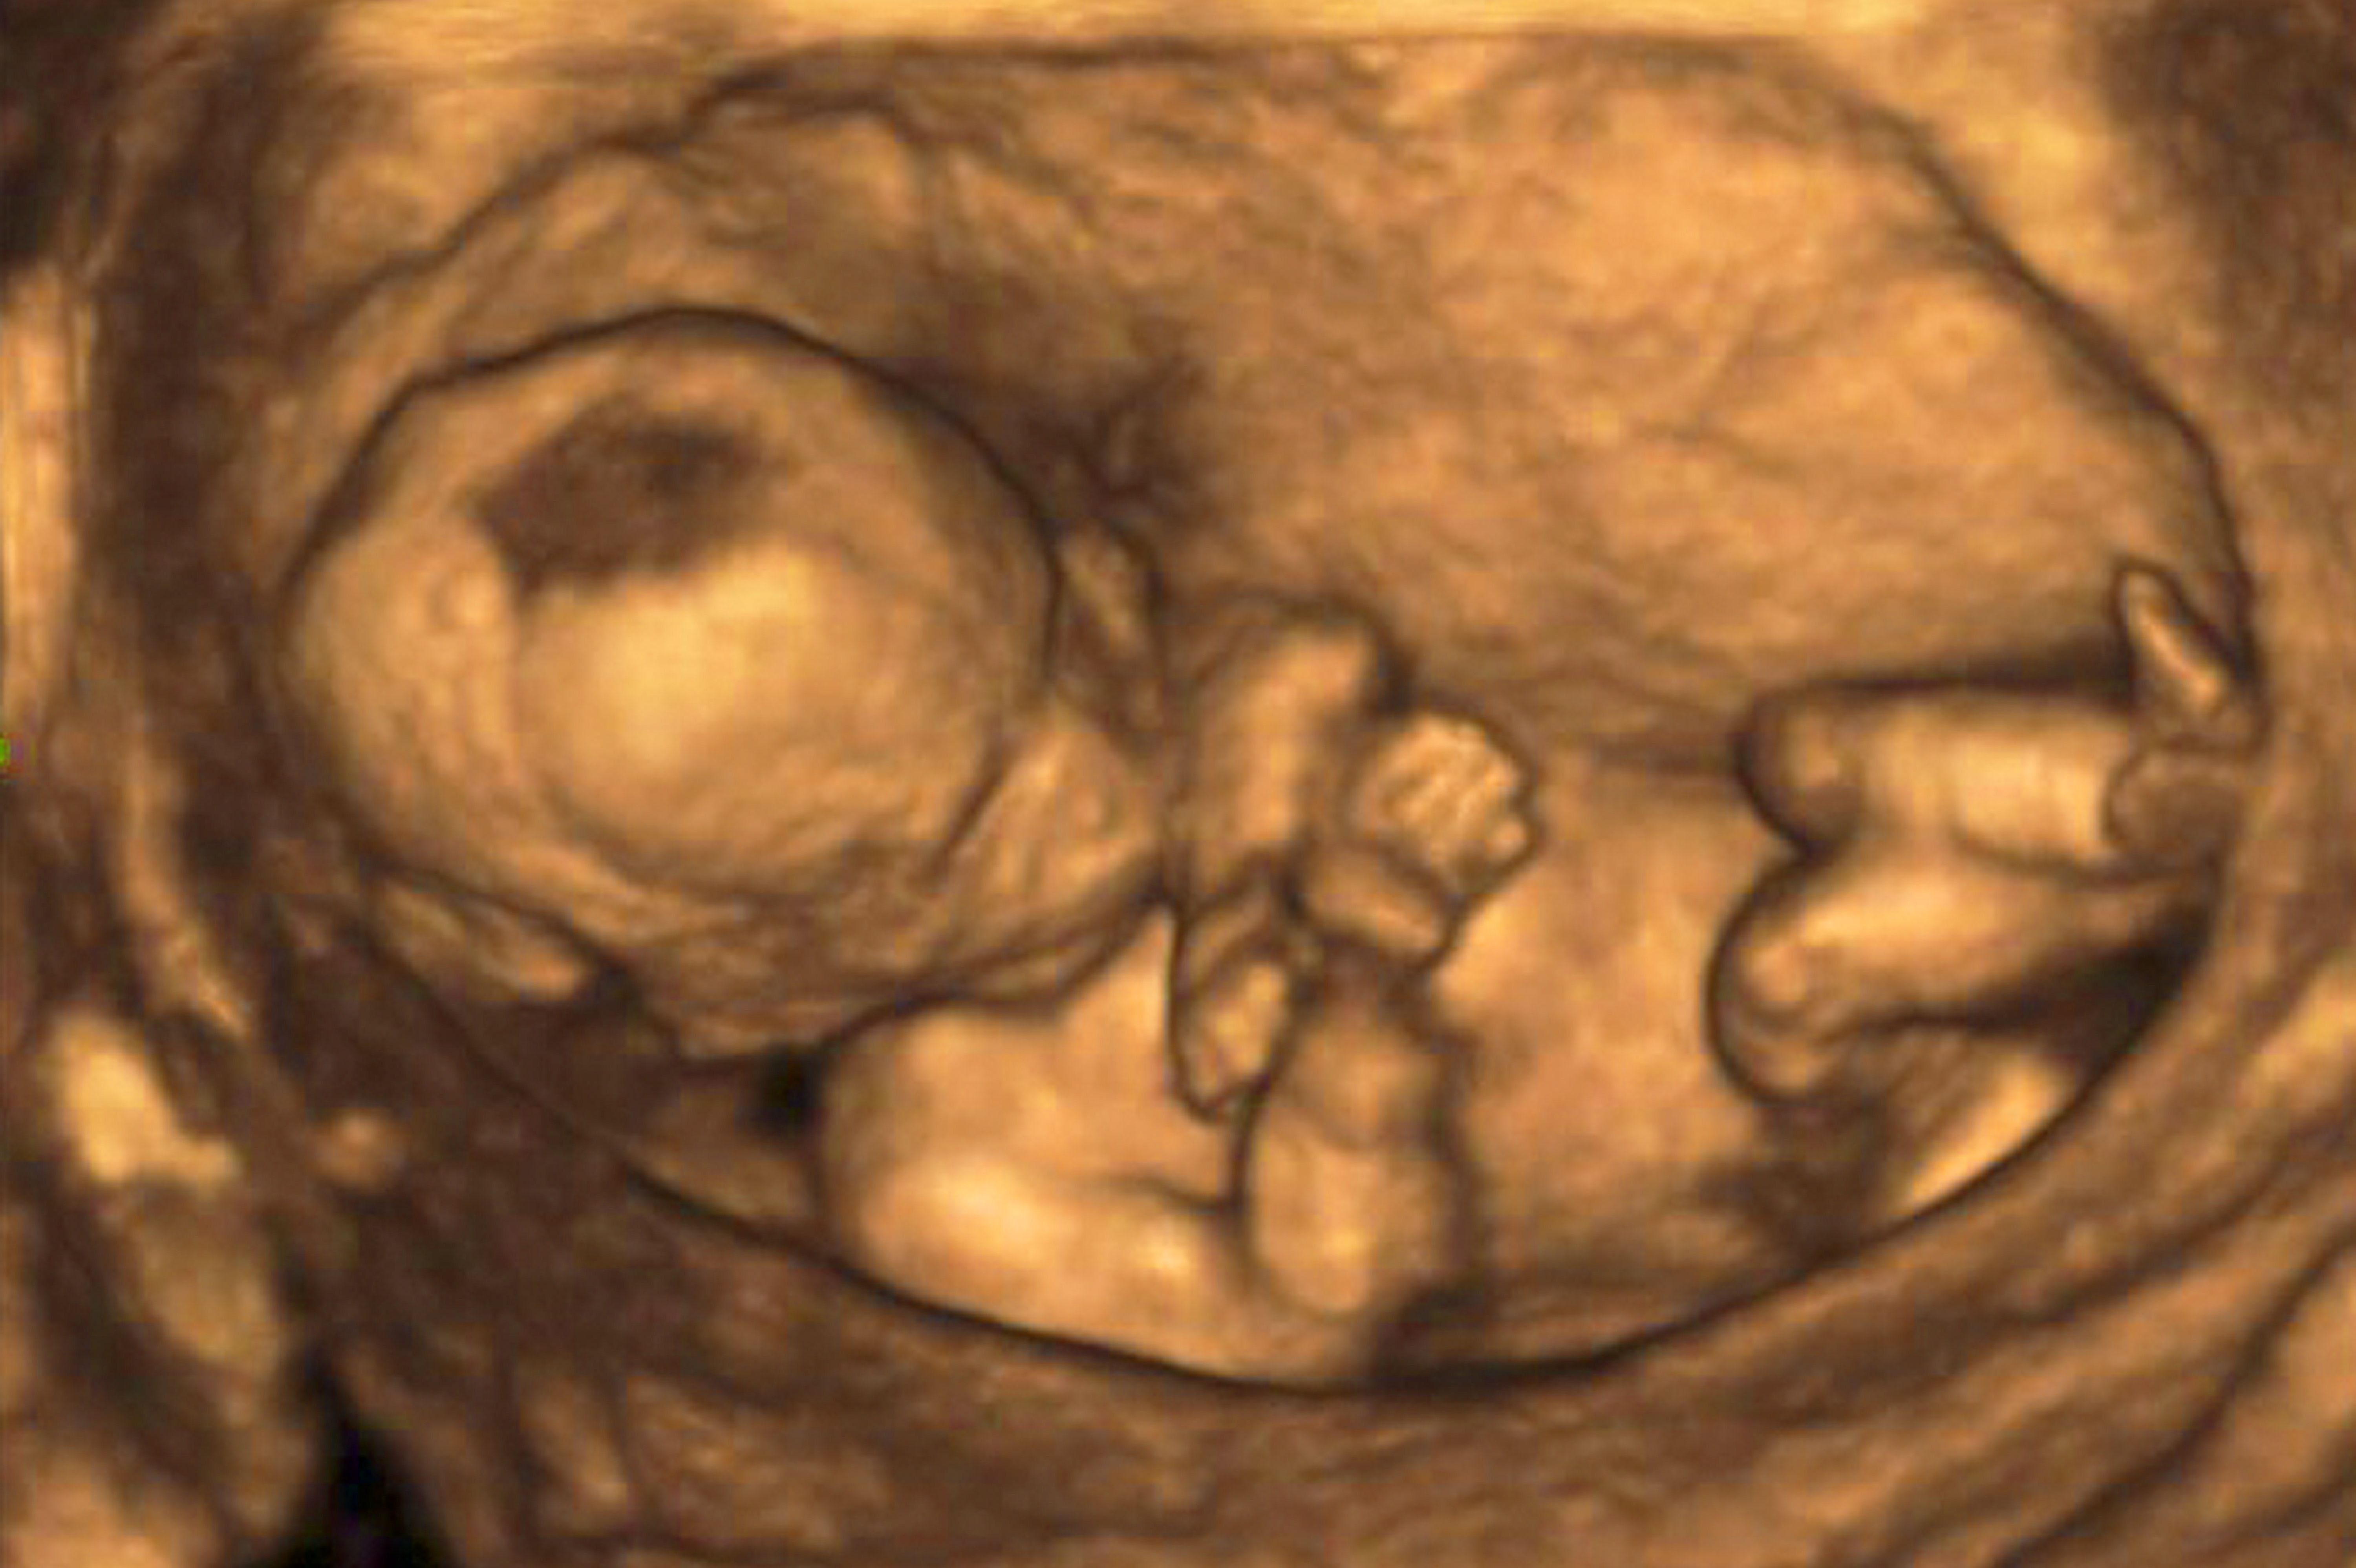

(Vienna, 28 January 2021) The internationally renowned TRUFFLE 2 study (trial of randomized umbilical and fetal flow in Europe) has kicked off at the Medical University of Vienna's Division of Obstetrics and Feto-Maternal Medicine. The aim of the study is to define the best management of fetuses with late onset fetal growth restriction. The study will be coordinated by Christoph Lees from Imperial College London and conducted at 60 centres throughout Europe. Julia Binder will lead the study at MedUni Vienna.

"Late onset fetal growth restriction is a major risk factor for intrauterine death, neonatal morbidity and poor long-term neurological outcomes for the affected children," explains Julia Binder, head of the outpatient clinic for fetal medicine at the Division of Obstetrics and fetomaternal Medicine at the Medical University of Vienna. Currently, there are no clear study results to indicate the preferred mode of management for late onset growth restricted fetuses – watch-and-wait management with close ultrasound monitoring or premature delivery. However, this is a decision with far-reaching consequences, since unsatisfactory early delivery or late delivery can seriously impact the long-term health of these children.